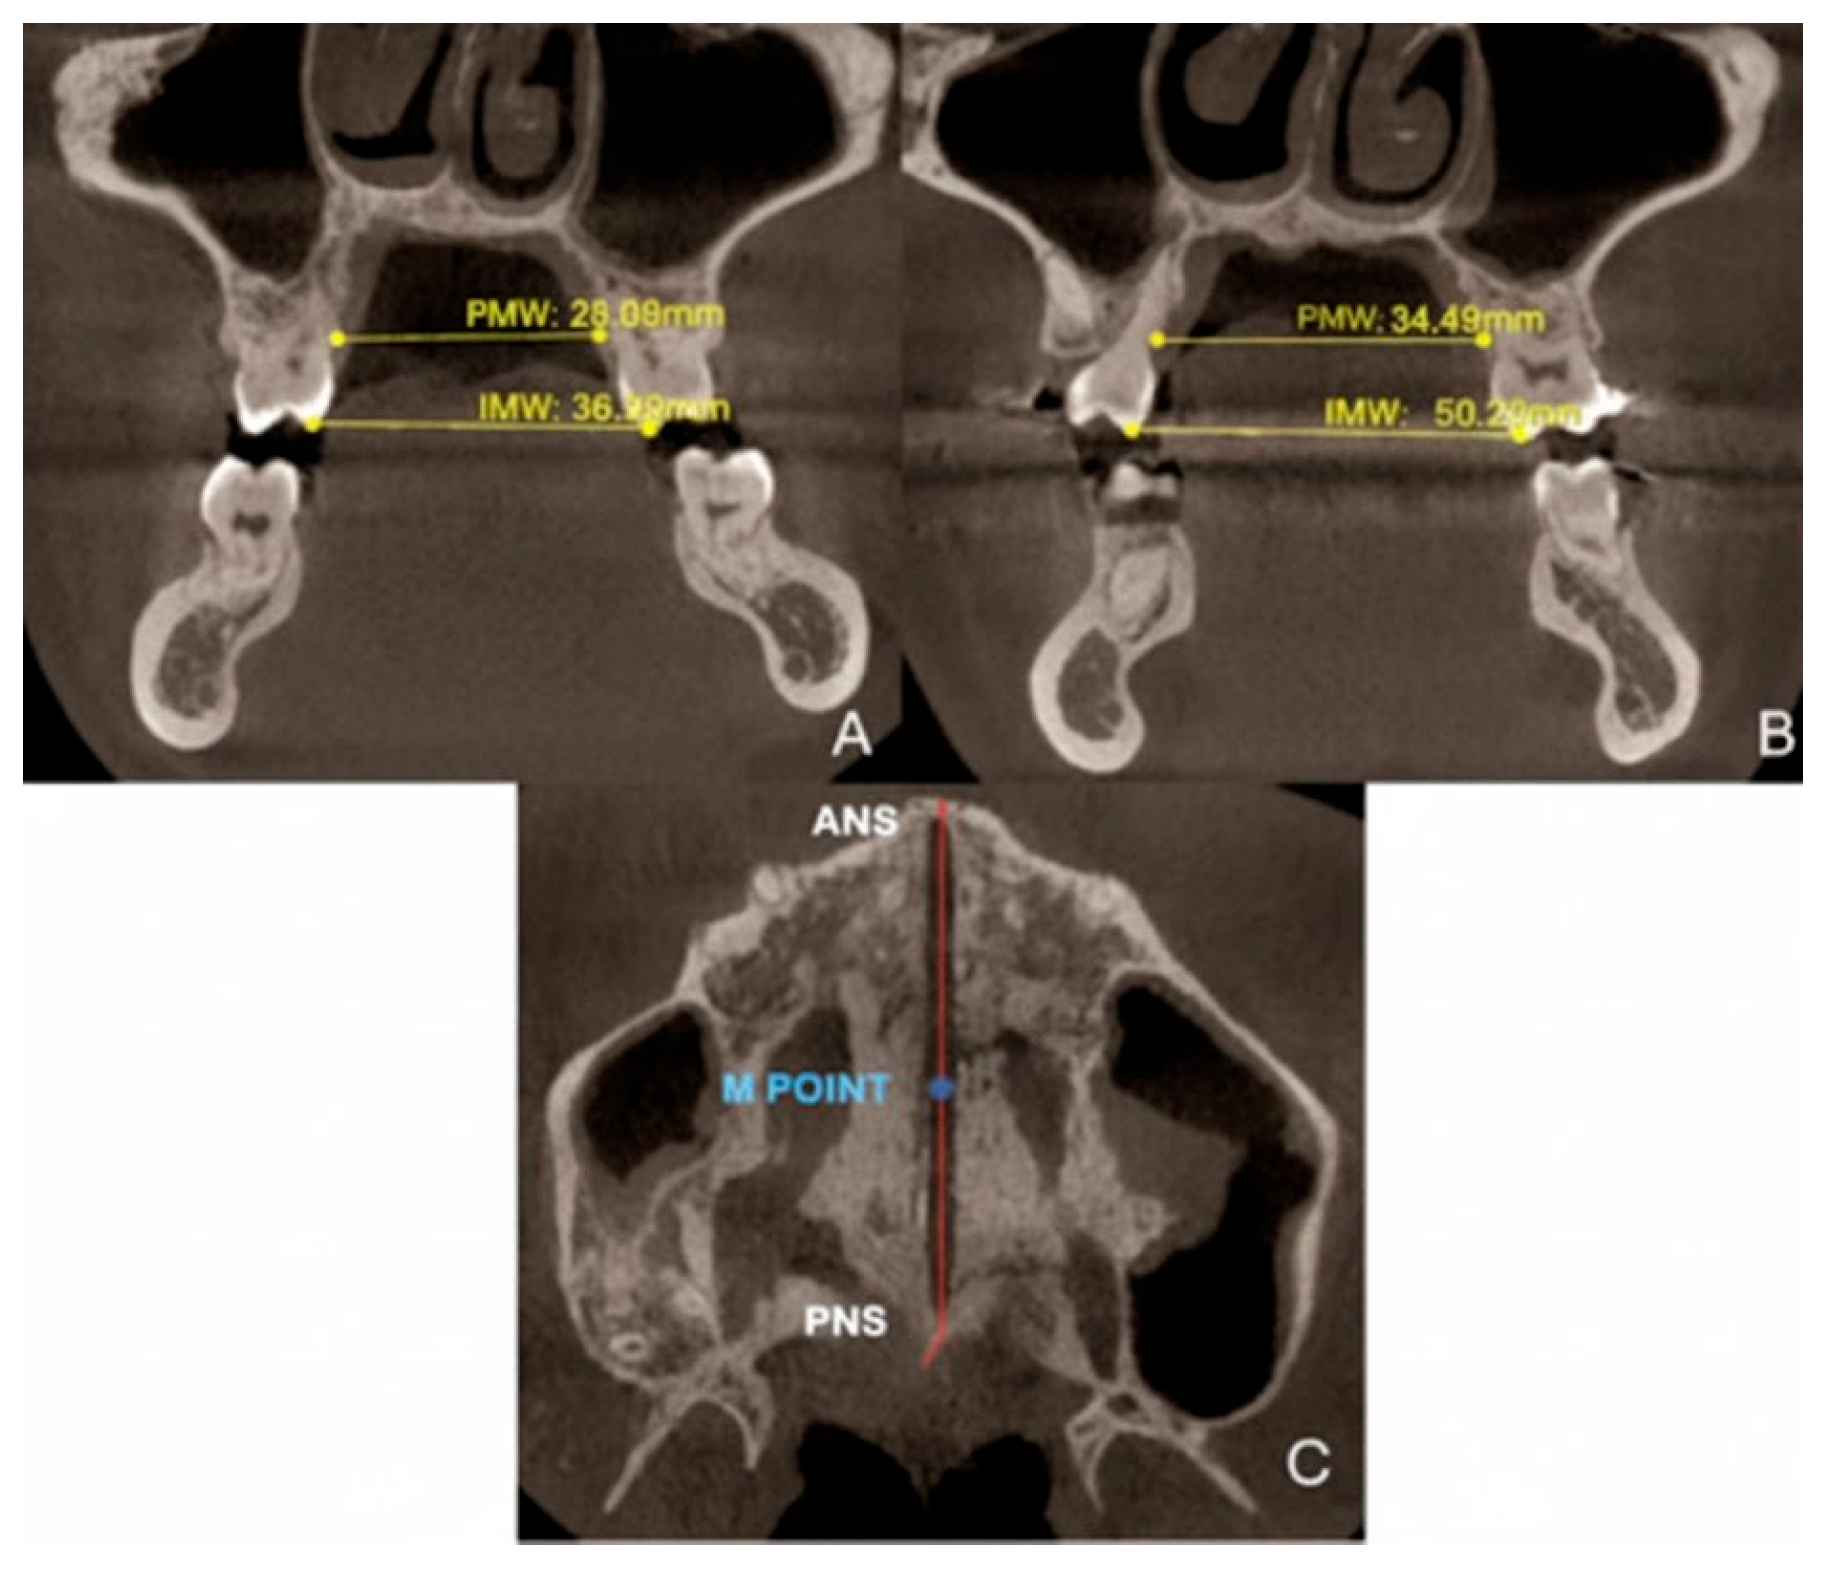

| Measurements | Pre-Treatment | Post-Treatment |

|---|---|---|

| PMW (mm) | 28.04 | 34.5 |

| IMW (mm) | 36.08 | 50.02 |

| SE (mm) | 0.32 | 7.82 |

3.3. Quantitative Two-Dimensional Analysis of Upper Palatal Expansion on CBCT